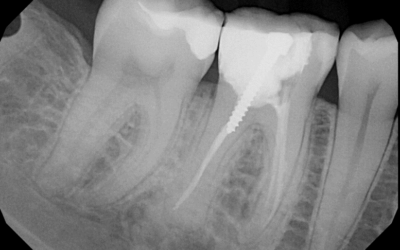

Root Canals

If infection has spread to the nerve of a tooth, it has the potential to spread to other teeth as well as your jaw. In this scenario, the tooth may need a root canal. The inner part of a tooth is called the pulp, and it has two major functions. One is that it has...